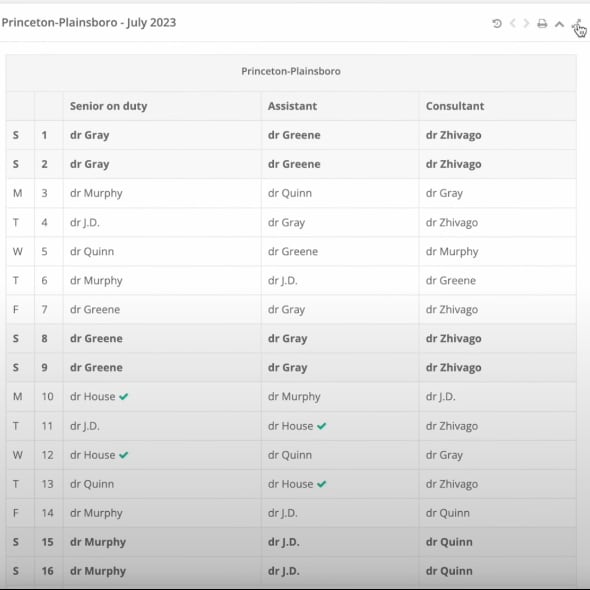

Cloud Medical was a healthcare IT startup building two core products: AMIgo — a management system for interventional cardiology departments covering procedure tracking, device inventory, and outcome reporting; and InPra — a specialist practice management platform handling patient scheduling, electronic health records, billing, and multi-location coordination. Both systems were cloud-based, GDPR-compliant, and designed for real clinical workflows.